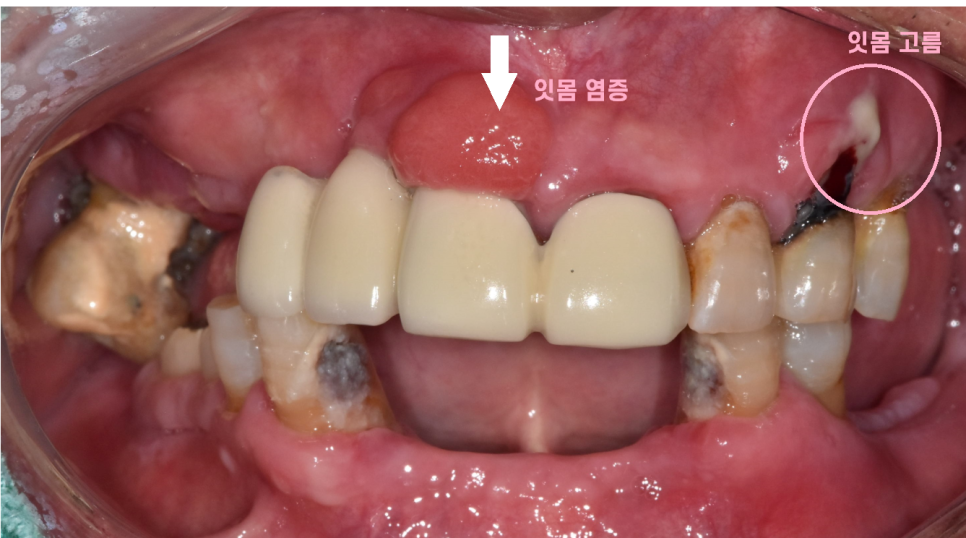

1차적으로 전반적인 잇몸 발적

빨갛게 부어오른 잇몸과

고름이 나오는 치아들

염증이 빠져나올 길이 없어 풍선처럼 부푼 잇몸도 관찰됩니다.

많이 아프셨는지

건들이기만 해도 통증을 호소하셨습니다.